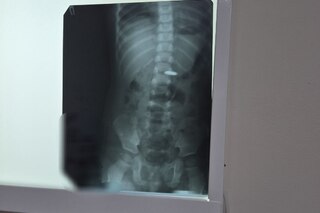

После рентгенологического подтверждения наличия батарейки в пищеводе или желудке, она незамедлительно удаляется с помощью эндоскопа. В случае проглатывания батарейки большого диаметра, она может застрять в привратнике желудка (месте, где желудок соединяется с кишечником) или зафиксироваться в кишечнике — тогда может потребоваться оперативное вмешательство.